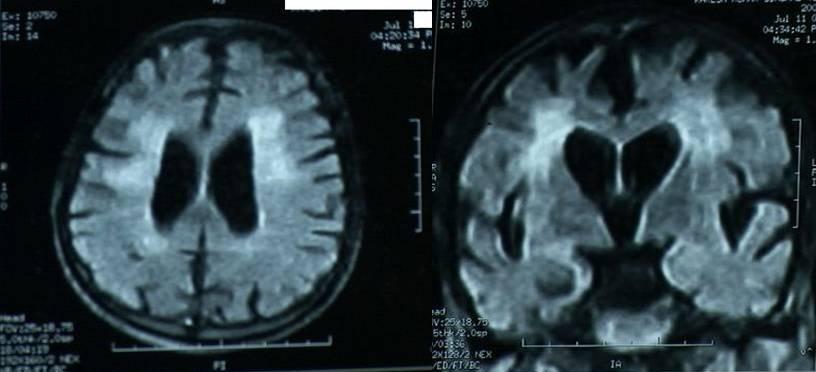

We present serial MRI studies in the case of a 45-year-old man who sustained an in hospital cardiac arrest and was successfully resuscitated after 25 minutes of cardiopulmonary resuscitation. Five years after the cardiac arrest he remains in a persistent vegetative state. Serial MRI studies (Fig 1 immediately and Fig 2 after 3 years and Fig 3 after 5 years of cardiac arrest) indicate ongoing cerebral atrophy and highlight the delayed effects of an initial anoxic injury.

Serial MRI axial and coronal sections studies (Fig 1 immediately and Fig 2 after 3 years and Fig 3 after 5 years of cardiac arrest) indicate ongoing cerebral atrophy and highlight the delayed effects of an initial anoxic injury.